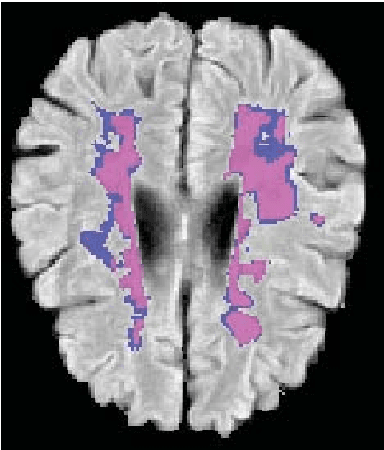

This paper explores the use of a soft ground-truth mask ("soft mask'') to train a Fully Convolutional Neural Network (FCNN) for segmentation of Multiple Sclerosis (MS) lesions. Detection and segmentation of MS lesions is a complex task largely due to the extreme unbalanced data, with very small number of lesion pixels that can be used for training. Utilizing the anatomical knowledge that the lesion surrounding pixels may also include some lesion level information, we suggest to increase the data set of the lesion class with neighboring pixel data - with a reduced confidence weight. A soft mask is constructed by morphological dilation of the binary segmentation mask provided by a given expert, where expert-marked voxels receive label 1 and voxels of the dilated region are assigned a soft label. In the methodology proposed, the FCNN is trained using the soft mask. On the ISBI 2015 challenge dataset, this is shown to provide a better precision-recall tradeoff and to achieve a higher average Dice similarity coefficient. We also show that by using this soft mask scheme we can improve the network segmentation performance when compared to a second independent expert.